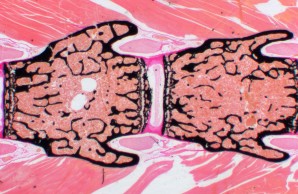

Forensic Osteology

Prof. Dr. med. Michael AmlingThe forensic osteology at the IOBM is an interdisciplinary division between forensic medicine and osteology. The investigation of bone and its reaction to external and internal influences (e.g. violence, hunger, un/loading, diseases, medication) facilitates conclusions with regard to the circumstances that a person was exposed to locally or systemically. Furthermore these investigations allow for the evaluation of the causes and temporal progression of skeletal injuries.

The scope of the division of forensic osteology ranges from the assessment of current cases to paleontological studies.